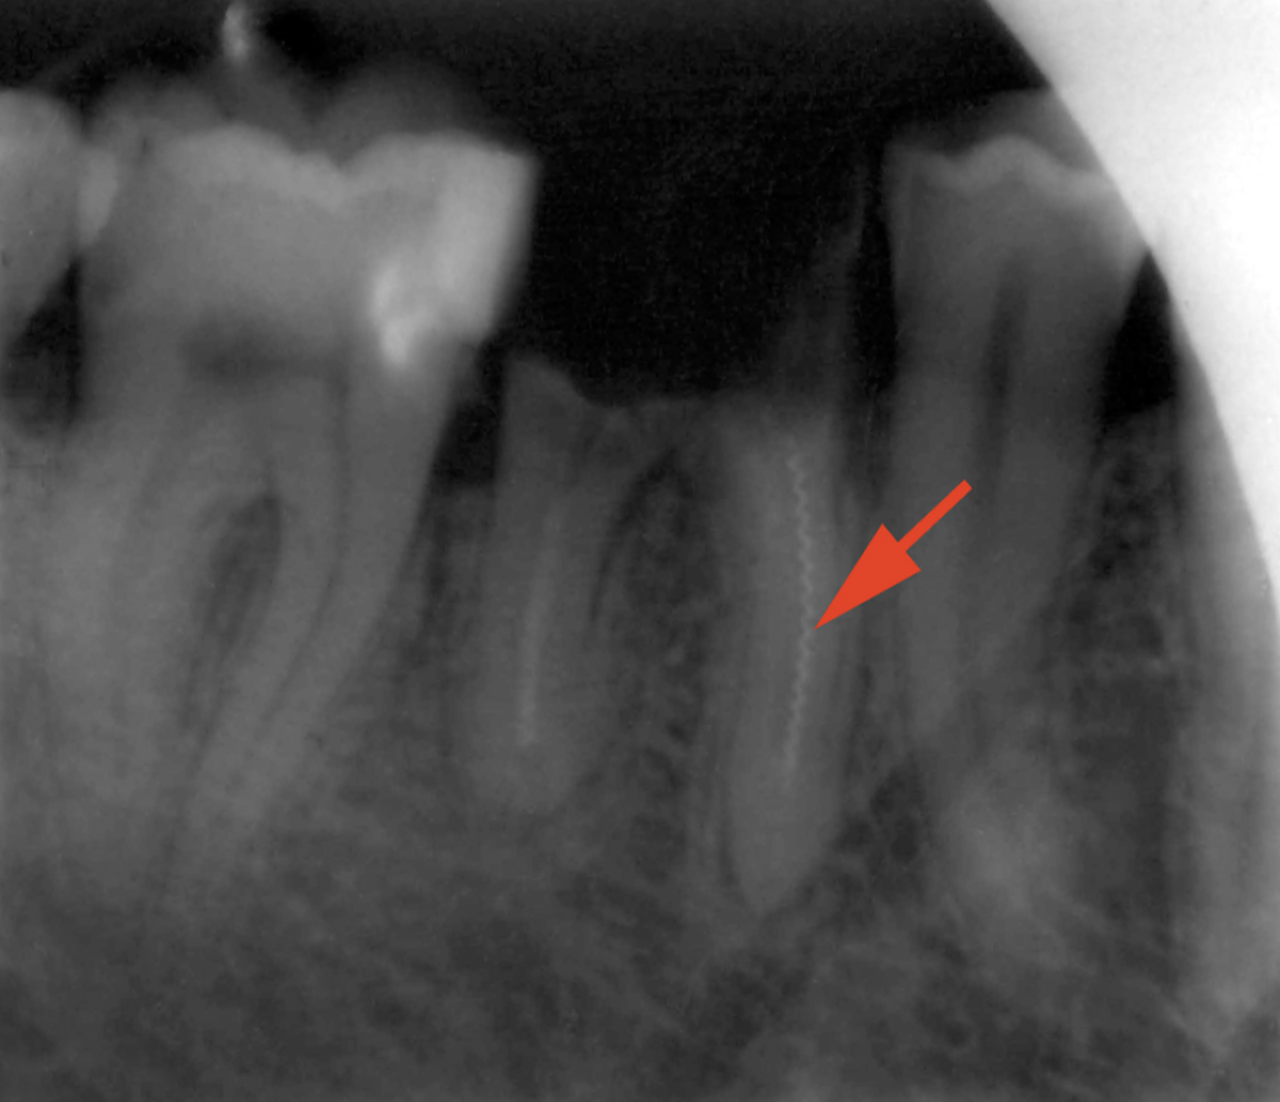

Резекция верхушки корня

Резекция верхушки корня зуба – это зубосохраняющая операция с удалением верхней части зубного корня